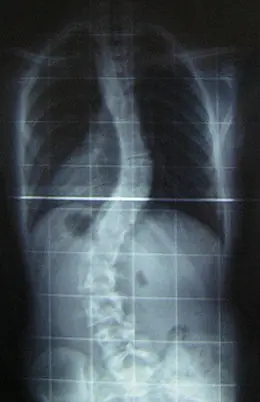

Clasificación

La escoliosis se clasifica en tres grandes grupos dependiendo de la causa:

* Escoliosis idiopática: constituyen más del 80% de todas las escoliosis y su causa es desconocida. Según la edad en que es diagnosticada, se divide en tres tipos: